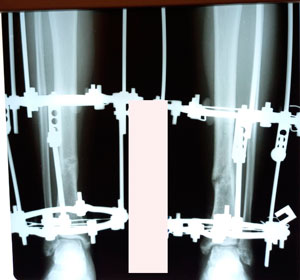

на фиксации

image-23-09-20-11-35.jpg

image-23-09-20-11-35-3.jpg